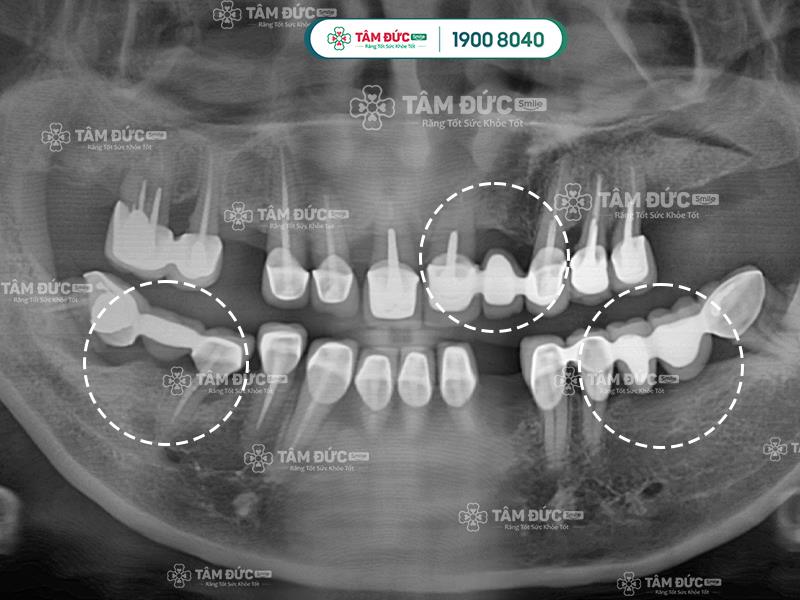

Cầu răng sứ không thể ngăn chặn tình trạng tiêu xương hàm khi mất răng